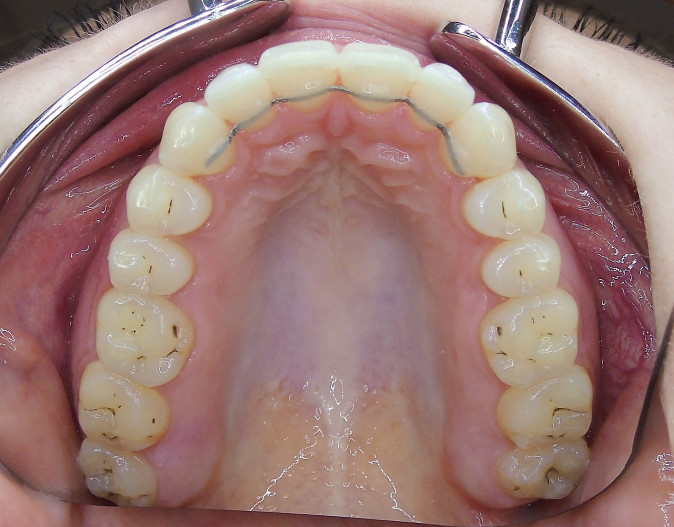

Der extraorale Befund (Abb. 1a–c) ergab ein gerades Durchschnittsgesicht mit leicht vergrößertem Nasolabialwinkel, ein symmetrisches Gesicht bei potenziell inkompetentem Lippenschluss sowie einen dolichofazialen Gesichtstyp. Intraoral lag beidseits annähernd eine Angle-Klasse I mit frontal offenem Biss (–2,5 mm) sowie ein dental-transversal zu schmaler Oberkiefer vor, woraus ein Kopfbiss von 13 und 23 resultierte. Des Weiteren zeigten sich ein persistierendes viszerales Schluckmuster und eine Inkongruenz der Kiefermitten (Abb. 2a–e; Abb. 3).

Aufgrund der latenten Zungendysfunktion war ein stabiles Rezidivkonzept obligatorisch. Deshalb wurden in beiden Kiefern Sechs-Punkt-Retainer geklebt und zusätzliche Retentionsschienen angefertigt. Okklusion und ästhetisches Erscheinungsbild konnten relevant verbessert werden.

Sechs Monate nach Abschluss der Therapie besteht weiterhin ein stabiles Ergebnis. Wie im Vergleichsbild (Abb. 5a–c) zu sehen ist, konnte die geplante vertikale Korrektur vollständig erzielt und die Mittellinie bis auf eine MLV von 1 mm nach rechts im UK korrigiert werden.